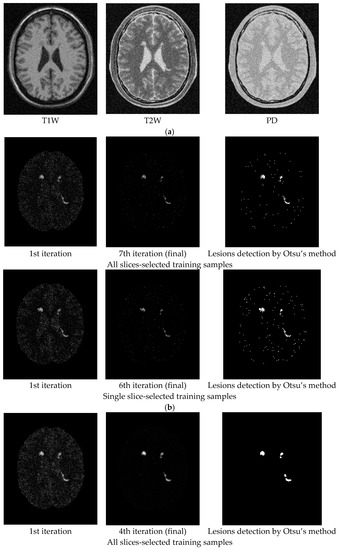

For an illustrative purpose, Figure 5, Figure 6, Figure 7, Figure 8, Figure 9 and Figure 10 only show detection results of WMH lesions of the 97th MR image slice with six levels of noise and 0% INU by two versions of CBEP-ICEM, using the Gaussian window size of specified by σ = 0.1 and the Gaussian window size of specified by σ = 0.5, referred to as CBEP-ICEM1 and CBEP-ICEM2, respectively, where two sets of training samples selected by all slices and the single 102nd slice were used to calculate the desired target signatures d to implement NBE-ICEM. As we can see by visual inspection against the ground truth in Figure 4d, CBEP-ICEM1 and CBEP-ICEM2 using two sets of training samples, i.e., all slices-selected and single slice-selected training samples, produced very close results and they both also performed better lesion detection than LST did.

Figure 8.

Lesion detection of Slice 97 with 5% noise and 0% INU by CBEP-ICEM1 and CBEP-ICEM2. (a) Original 97th slice of MS MR brain images with 5% noise and 0% INU; (b) CBEP-ICEM1; (c) CBEP-ICEM2; (d) Lesion detection LST.

Figure 9.

Lesion detection of Slice 97 with 7% noise and 0% INU by CBEP-ICEM1 and CBEP-ICEM2. (a) Original 97th slice of MS MR brain images with 7% noise and 0% INU; (b) CBEP-ICEM1; (c) CBEP-ICEM2; (d) Lesion detection LST.

Figure 10.

Lesion detection of Slice 97 with 9% noise and 0% INU by CBEP-ICEM1 and CBEP-ICEM2. (a) Original 97th slice of MS MR brain images with 9% noise and 0% INU; (b) CBEP-ICEM1; (c) CBEP-ICEM2; (d) Lesion detection LST.